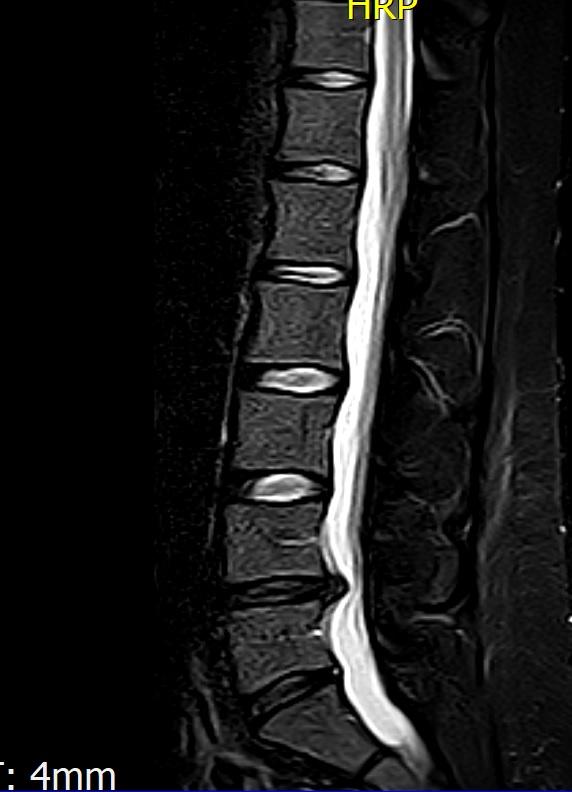

1. Also ich komm jetzt gerade vom MRT. Hier sieht man ja den Schaden ganz gut, habe einen Bandscheibenvorfall. Im Moment tut es nicht weh, hab die letzten Tage zu Hause jeden Tag den Unterarmstütz gemacht und mit der Faszienrolle gearbeitet, denke das hat geholfen. Jetzt habe ich seit einer Woche eine neue Arbeit und stehe den ganzen Tag vor einer Maschine, sitzen ist nicht machbar denn dann kann ich nix arbeiten. Hat da jemand Tipps?